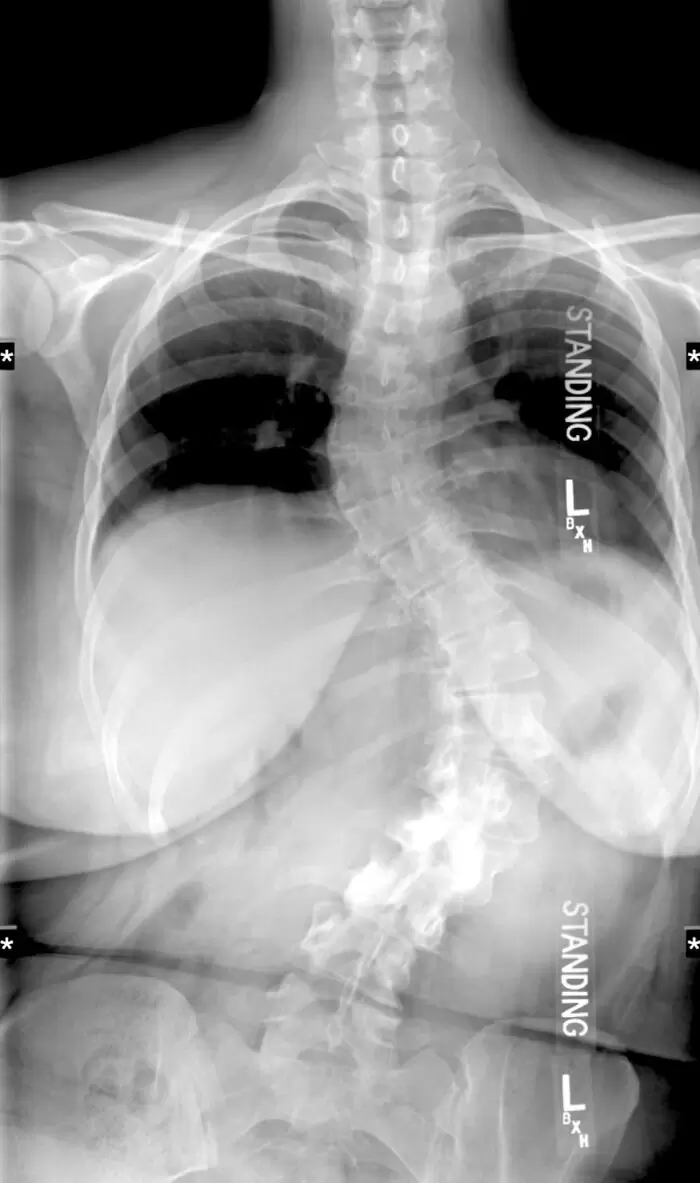

▼希望留下這張X光照片的人一切安好

圖片來自:reddit